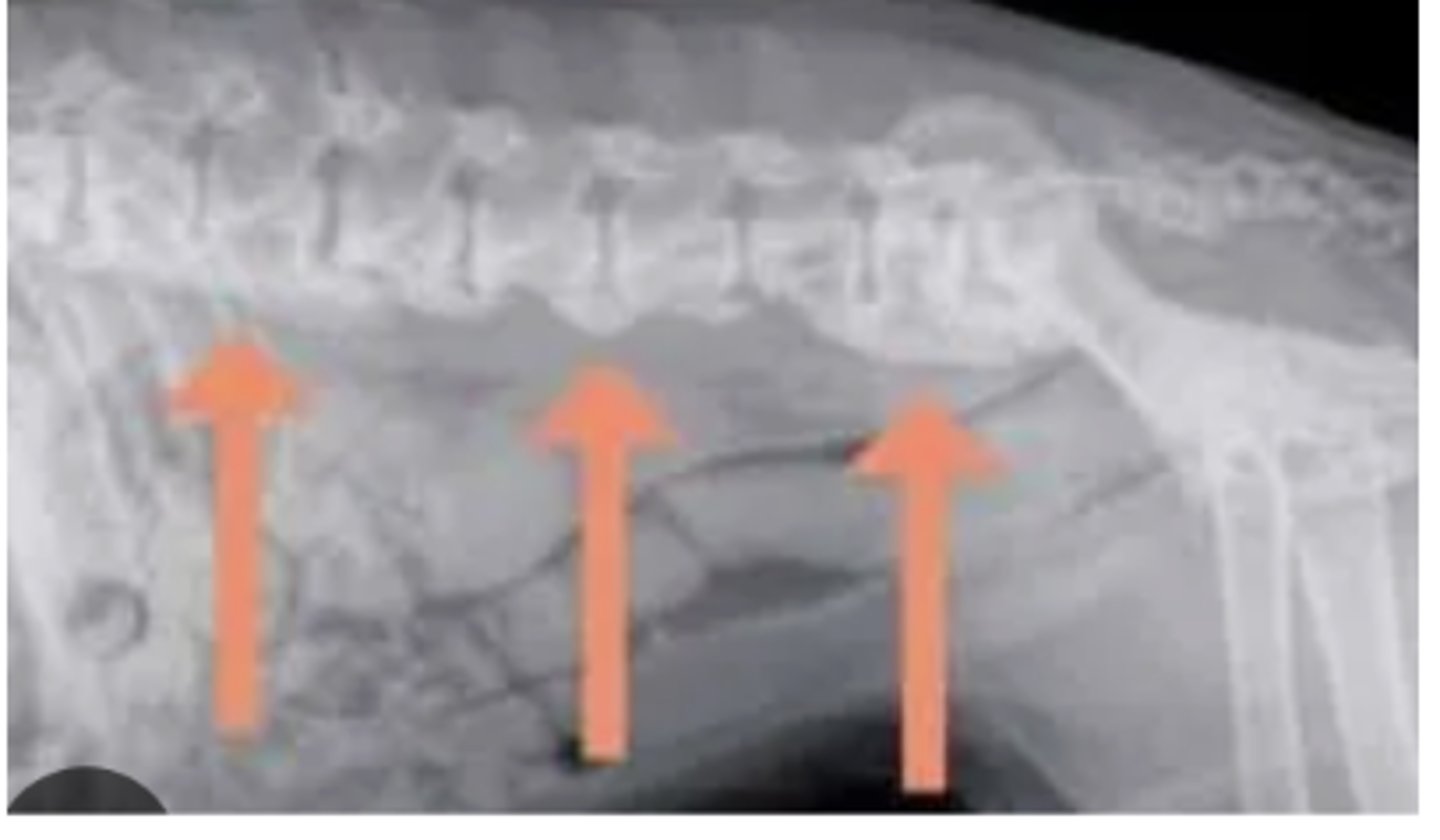

Spondylosis deformans

What abnormality is shown in this radiograph of the spine?

narrowed intervertebral space

What is seen in IVDD?